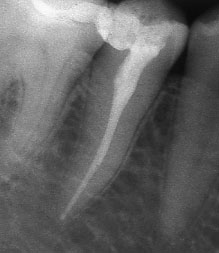

При добре проведено ендодонтско лечение кореновият канал е запълнен точно до стеснението, разположено на 1 - 1.5 мм. от края на канала - т.нар. физиологично стеснение. Не бива да остава незапълнена част от канала. Много често се получава припресване на канлопълнежното средство извън канал на зъба, в тъканите около корена.

Ако при диагностична рентгенография се установи, че даден канал не е запълнен до физиологичното стеснение, е необходимо да се проведе повторно ендодонтско лечение.

В някои случаи недобре запълненият коренов канал е показание дори за отстраняване на протезни конструкции (корони и мостове) в които е включен съответният зъб.

Винаги е необходимо лекуващият да се стреми към този резултат: